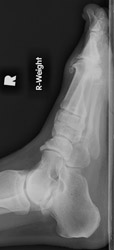

Osteoarthritis: Lateral View - Large dorsal osteophytes at 1st MTP jointOsteoarthritis: AP View - Large osteophytes and joint space narrowing at 1st MTP jointOSTEOARTHRITIS non-inflammatory deterioration of articular cartilage with articular surface and marginal bone formation.

Radiographic manifestations may include marginal osteophyte and subchondral bony cyst formation, eburnation, and interosseous joint space narrowing. First metatarsal phalangeal joint osteoarthritis is frequently associated with hallux valgus deformities. Calcaneal spurs, when manifested, are sharp and well defined.